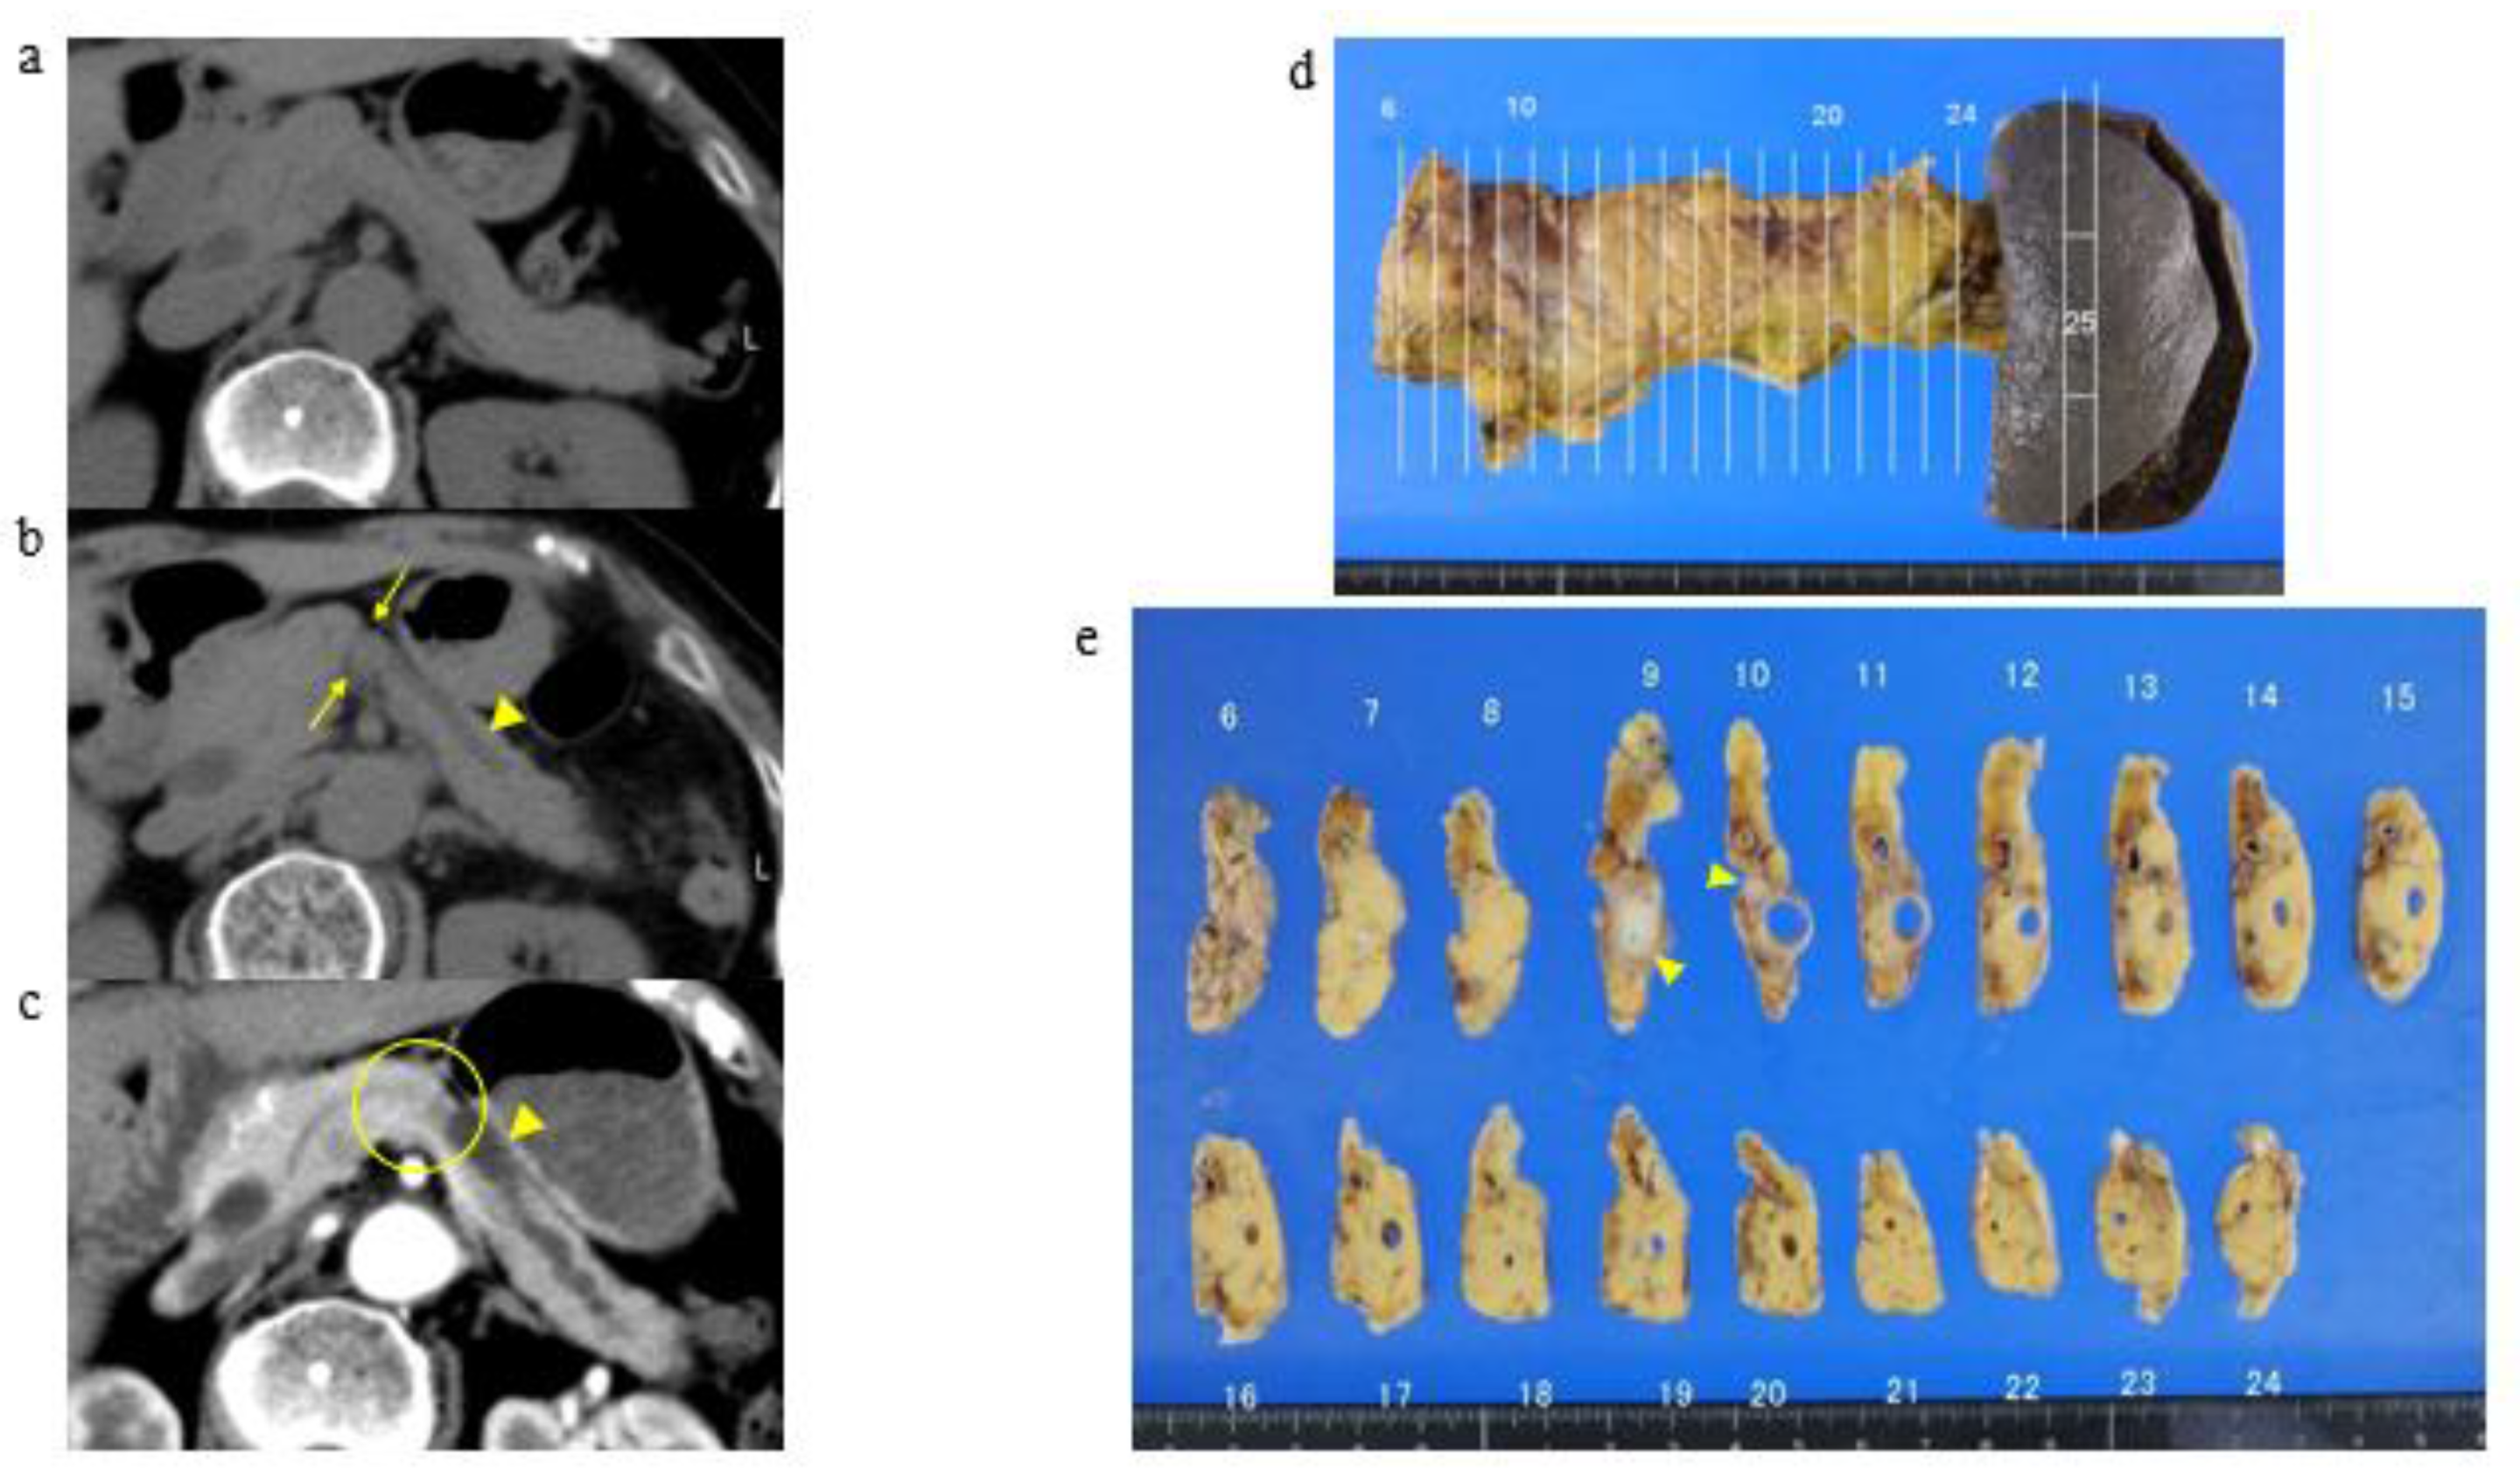

3.2. A Representative Case and Classification by Specific Abnormality of the Pancreas